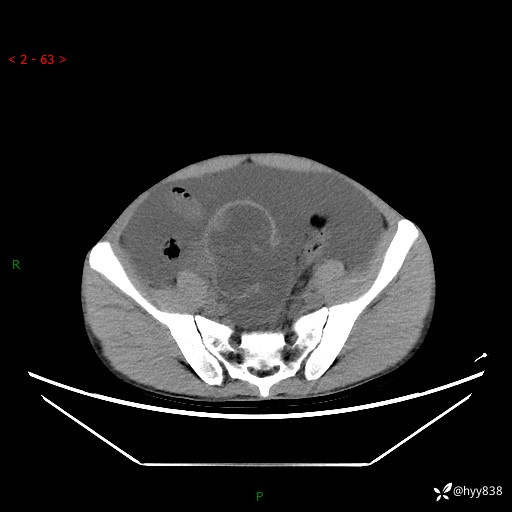

现病史:患者10天前无明显诱因出现腹部胀痛不适,无畏寒发热,无胸痛胸闷,无心慌气短,无恶心呕吐,无腹泻及黑便,无粘液血便及里急后重等症状,4天前在当地县人民医院就诊,行腹部CT示:下腹部占位性病变,腹腔及盆腔积液;今患者为求进一步诊治来我院治疗,门诊以“腹水”收治入院。 发病以来,精神饮食可,大小便正常,体重体力无明显变化。

腹部CT平扫+增强